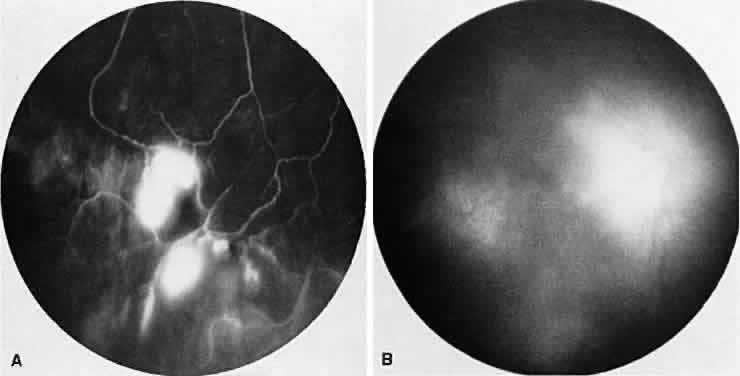

SARCOIDOSIS

Fig. 7. Sarcoidosis. A. Choroidal granuloma. B. Fluorescein angiogram shows staining of the choroidal granuloma.

The FA reflects the various clinical entities. Retinal venular walls stain, particularly where there are perivenular exudates.25–27 More extensive venous involvement can produce a picture of dilated veins and perivenous leakage.27 Peripheral neovascularization occurs near areas of retinal capillary nonperfusion.25,28 Optic disc granulomas and optic disc neovascularization both leak extensively (Fig. 8A); sarcoid retinal lesions also stain (see Fig. 7B).27 In disc edema, the disc is hyperfluorescent and leaks fluorescein (see Fig. 8B).25

Fig. 8. Sarcoidosis. A. Fluorescein angiography shows two separate areas of neovascularization of the peripheral retina. B. Extreme leakage of dye from the right disc with cystoid macular edema of the right macular region in a patient with chronic sarcoidosis.

Four main patterns can be identified with ICG angiography. The first and most common pattern is hypofluorescent dark spots in the early and intermediate phases of the angiogram. These spots either become isofluorescent or remain hypofluorescent in the late phases. The second pattern is focal hyperfluorescent spots seen in the intermediate and late phases. The third pattern is fuzzy choroidal vessels due to perivascular choroidal leakage in the intermediate phase. Finally, the fourth pattern is characterized by diffuse zonal hyperfluorescence representing choroidal staining in the late phase of the angiogram. The latter two patterns resolved after systemic corticosteroid treatment.29